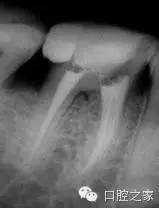

在1990年,Carlsen 和 Alexander 就曾經(jīng)報(bào)道了398例下頜第一恒磨牙舌側(cè)額外牙根的研究。舌側(cè)額外牙根的宏觀結(jié)構(gòu)在根管形態(tài)和彎曲度上表現(xiàn)出高度變異性。當(dāng)?shù)谌栏奈恢迷陬a側(cè)時(shí),被稱之為副磨牙。其根管形態(tài)和彎曲度有非常高的變異度(圖1b)。典型的代表是,牙根的軸朝向磨牙的頰側(cè)?;诖?,選擇遠(yuǎn)中頰尖作為參考指示點(diǎn),相對于經(jīng)典的選擇遠(yuǎn)中舌根作為參考點(diǎn)更為容易些。考慮到根管口與根尖1/3的頰側(cè)曲度之間所形成的斜率,這些都表明是高度復(fù)雜的根管,不利于根管預(yù)備與根管化學(xué)沖洗。為了避免出現(xiàn)意外事故,推薦使用小號(hào)的、高度彈性的根管銼來通暢根管,預(yù)備根尖部。